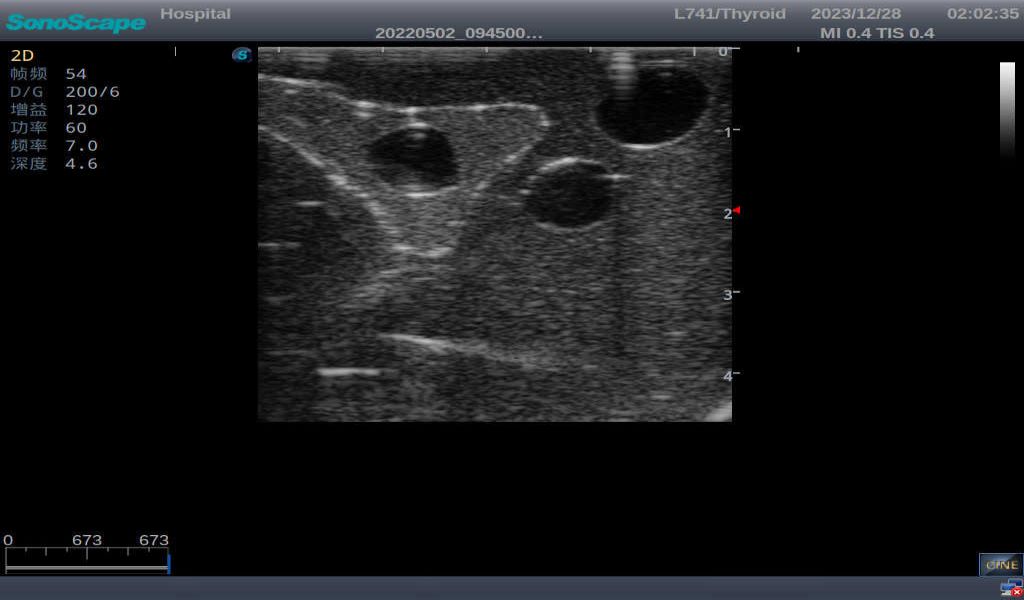

3)       It comes with four (4) thyroid modules and can show five (5) ultrasonic images: normal thyroid, thyroid adenoma, thyroid cancer, nodular goiter, thyroid cyst

Nodular goiter with irregular border and varying sizes of low echo, isoechoic, or high echo nodules